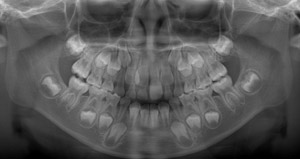

レントゲンからも、永久歯が生えるには顎のサイズが小さいことがわかります。